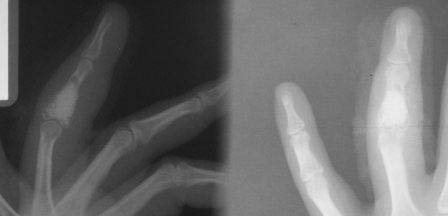

[Ortho] остеобластокластома

после первой операции